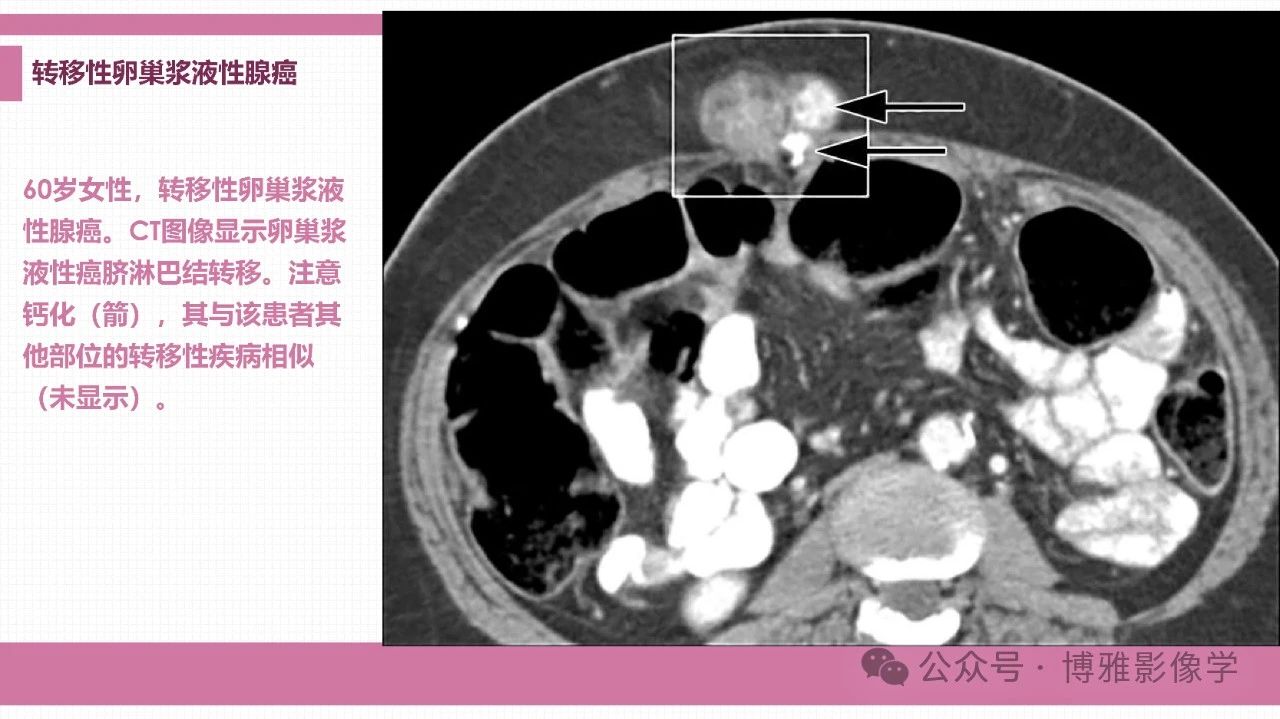

腹壁肿瘤、肿瘤样病变和弥漫性病变的影像学鉴别诊断思路

来源:博雅影像学

李福兴 天津市宝坻区人民医院